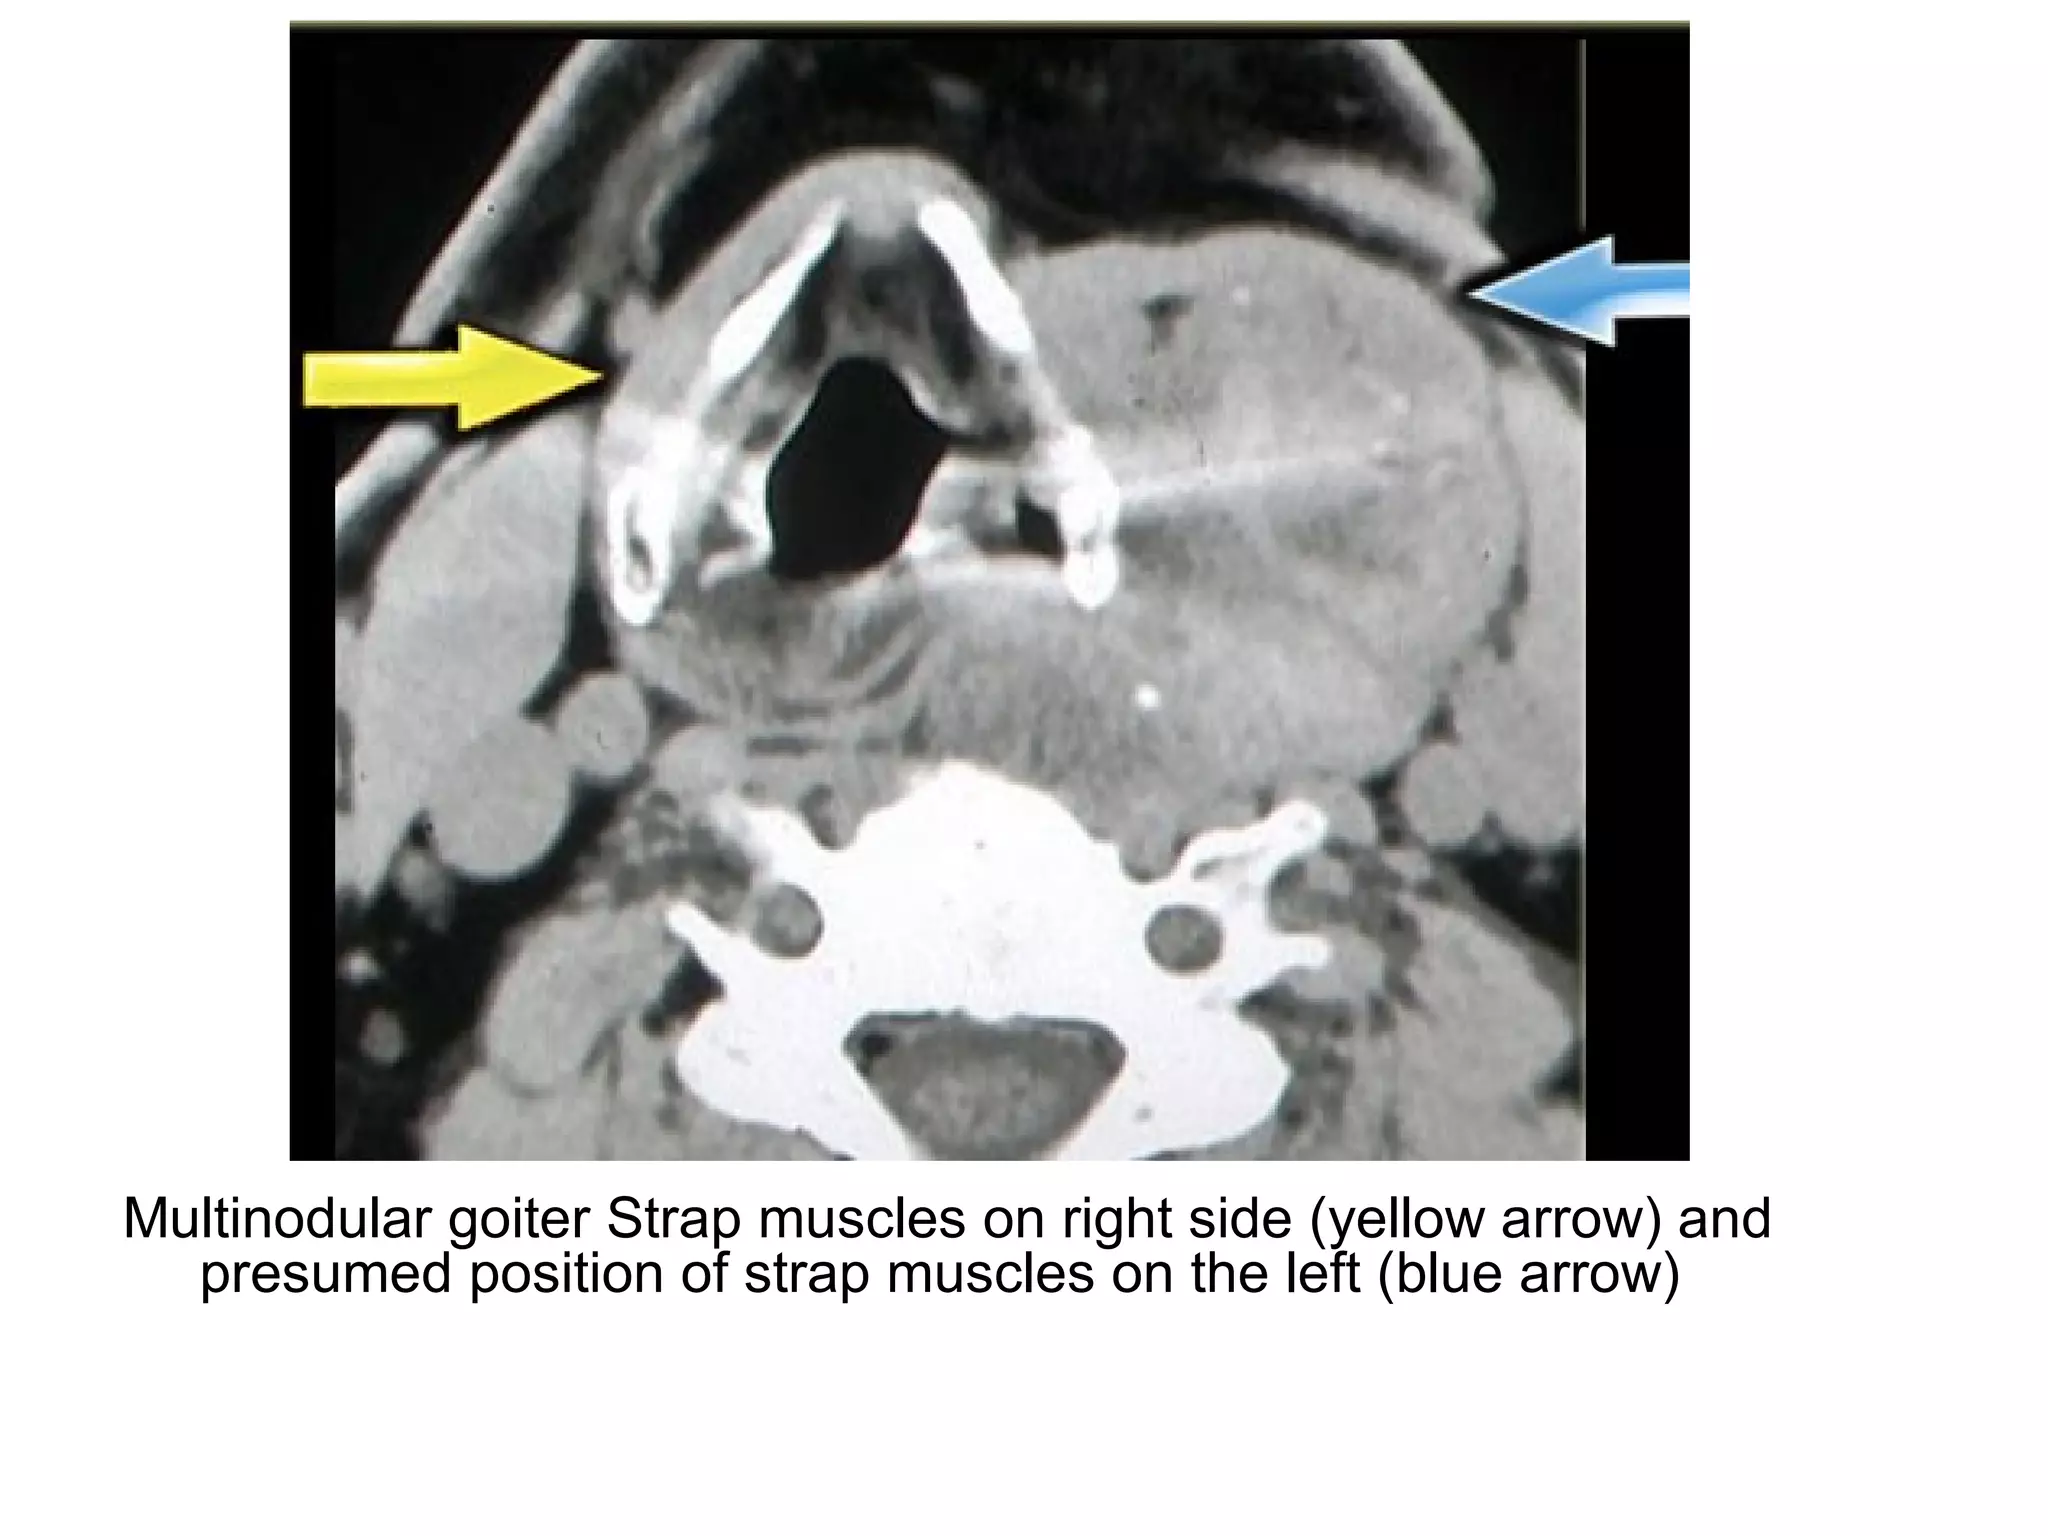

Multinodular goiter Strap muscles on right side (yellow arrow) and

presumed position of strap muscles on the left (blue arrow)

Multinodular goiter Strapmuscles on right side (yellow arrow) and presumed position of strap muscles on the left (blue arrow)